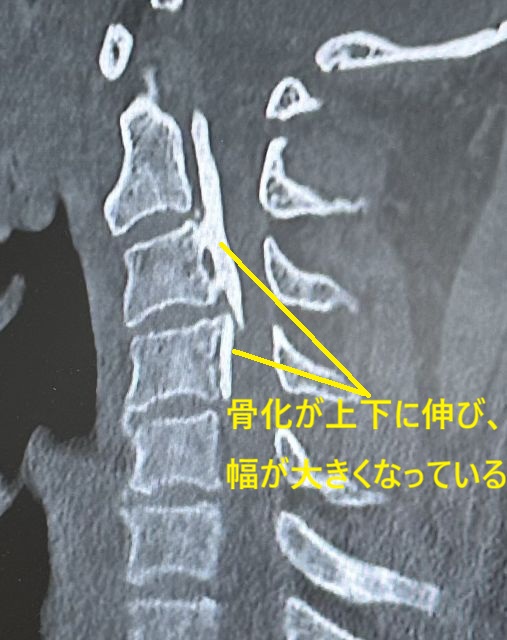

頚椎症性変化の進行とともに靭帯骨化が上下に広がったり (CT所見)、前後に厚くなると脊柱管が狭められます (CT所見)。そのような状態になると転倒や転落、外傷性頚部症候群をきっかけに頚髄や頚神経が障害され、脊髄症や神経根症を発症し、手指へ放散する痛みやシビレ、筋力低下、運動障害を認め、進行すると痙性歩行(足が麻痺して歩き難くい状態)や直腸膀胱障害(おしっこや便の出具合が悪い状態)も起こります。

診断はレントゲン検査で

後縦靭帯骨化が確認できれば容易です。(本来、後縦靭帯はレントゲンに写りません。骨化するとレントゲンに写ります)。さらに骨化の形態や脊髄の圧迫状態を詳細に検討するためにCT造影CTMRIなどが必要となります。